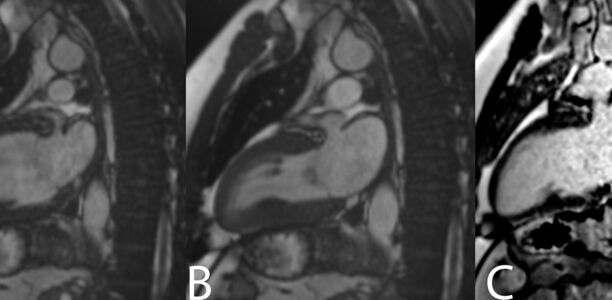

Kardiologische Rehabilitation bei einem 42-Jährigen nach peripherer Lungenarterienembolie im Rahmen einer SARS-CoV-2-Infektion

© Dr. med. Dietrich Stoevesandt, Universitätsklinik und Poliklinik für Radiologie, Universitätsklinikum Halle (Saale)

© Dr. med. Dietrich Stoevesandt, Universitätsklinik und Poliklinik für Radiologie, Universitätsklinikum Halle (Saale)